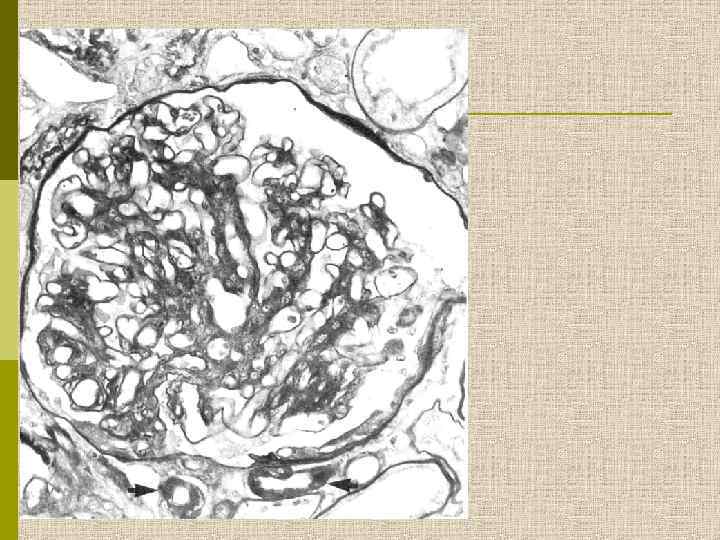

МОРФОЛОГИЧЕСКИЕ ИЗМЕНЕНИЯ ПРИ ДИАБЕТИЧЕСКОЙ НЕФРОПАТИИ Основные варианты - диабетический гломерулосклероз с узелками Kimmelstiel-Wilson - диффузный мезангиальный гломерулосклероз Характерные признаки Утолщение ГБМ; артериолярный гиалиноз; аневризматические капилляры; капсулярные капли; фибриновые шапочки; атрофия канальцев; инфильтрация, расширение и склероз интерстиция; линейные отложения иммуноглобулинов

Узелковый гломерулосклероз (болезнь Киммельстиля. Вильсона). Узелки pink гиалинового материала в области петель клубочковых капилляров – значительное уширение мезангиального матрикса в резельтате неэнзиматического гликозилирования протеинов.